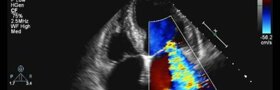

Ecocolordoppler cardiaco

Metodica diagnostica non invasiva

Consiste nell’esecuzione mediante una specifica sonda ecocardiografica di immagini e filmati che consentono di valutare:

- la morfologia,

- le dimensioni,

- la funzione,

delle diverse componenti del cuore (atri, ventricoli, miocardio, valvole).